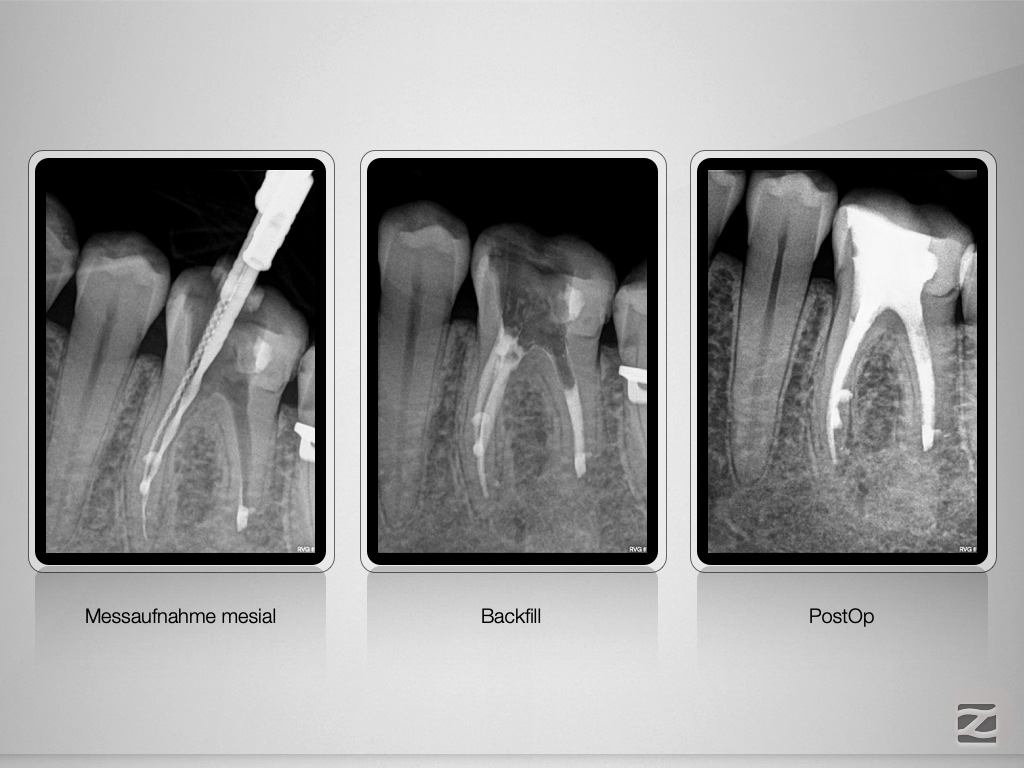

36D.009